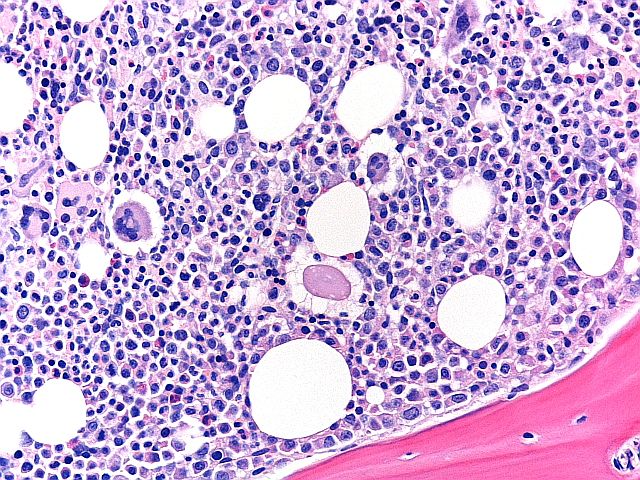

H&E - BMT Scheme

Ito ay isang mahusay na paghahanda ng isang BMT biopsy, na may balanseng H&E staining, magandang detalye ng chromatin, at selective staining ng mga uri ng cell sa loob ng bone marrow tissue. Ang slide na ito ay nakakuha ng 9/10 sa pagtatasa.